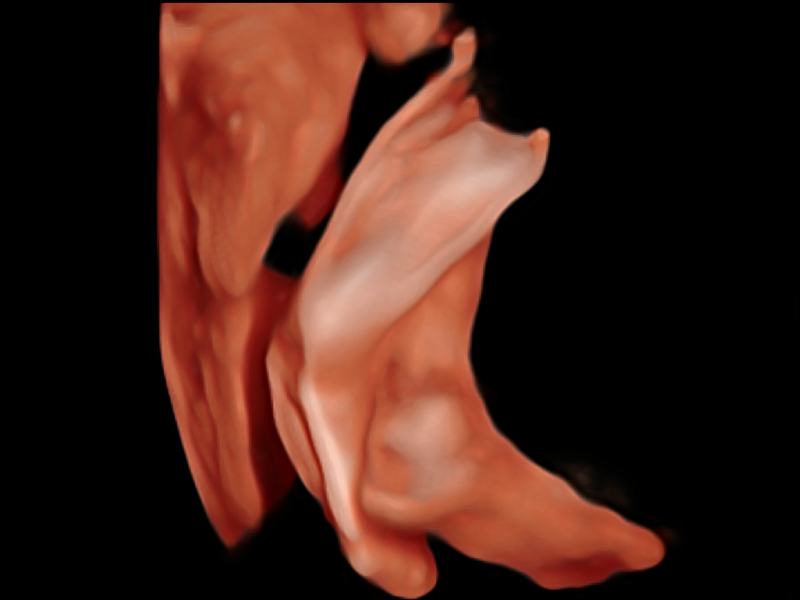

S-Fetus基于大数据深度学习算法,能够帮助您在产前筛查过程中智能识别胎儿标准切面、自动测量并录入报告。一个按键,即可智能、精准、高效地获取胎儿生理指标,极大简化您的产科检查操作。

可快速对产科扫查切面完成胎儿生理学参数的自动测量,减少操作者按键次数,大幅提升检查效率。